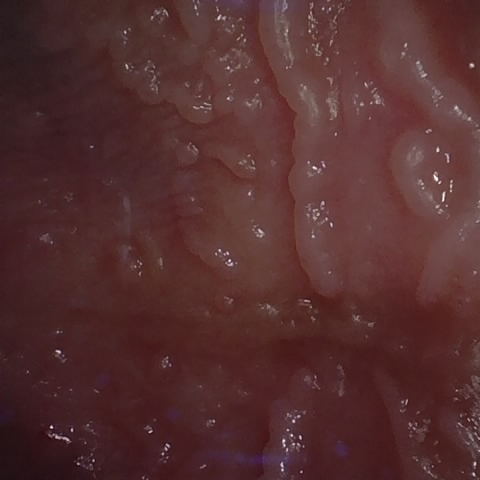

NHD39174

Annotated as "Good"

Original Image Rendering Image